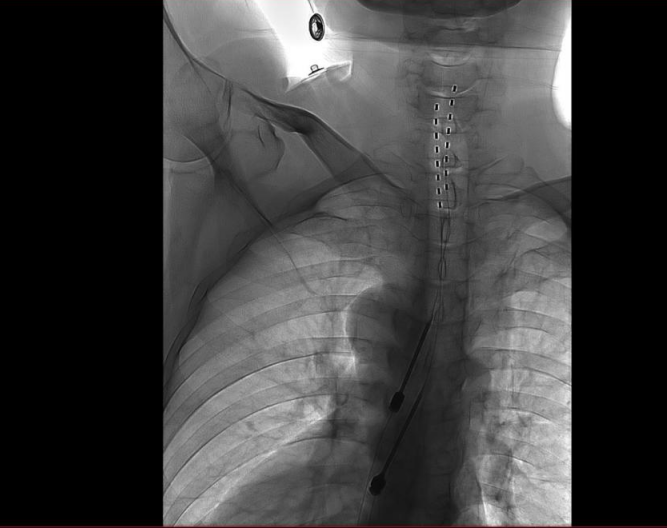

手術通過微創硬膜外腔穿刺技術,于DSA(數字血管剪影造影)引導下將極細的電刺激電極與植入式脈沖發生器共同植入體內。

手術歷經3小時,病人恢復良好。術后1周內,團隊根據患者疼痛緩解及感覺區覆蓋情況,對植入電極的刺激參數進行多次動態調控,目前廖先生疼痛明顯減輕,預計可于近期順利出院。